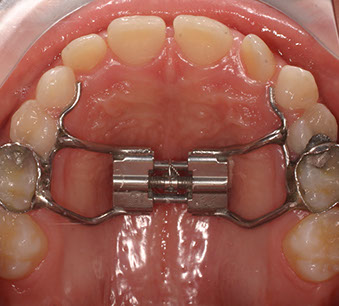

Talvolta, quando si vuole espandere l’arco palatino iposviluppato,  può essere necessario applicare un Diastasatore